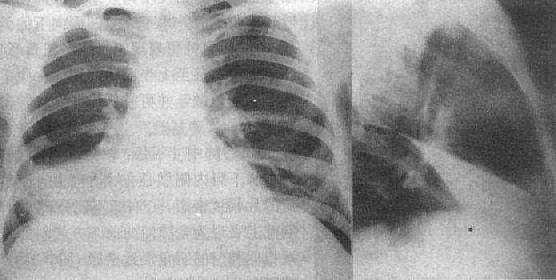

1.渗出与实变 机体的急性炎症反应主要表现是渗出(exudation)。渗出性病变的范围不同,在X线上表现为密度不太高的较为均匀的云絮状影,边缘模糊,与正常肺间无清楚界限(图3-1-10)。肺部急性炎症进展至某一阶段,肺泡内气体即被由血管渗出的液体、蛋白及细胞所代替,形成渗出性实变(consolidation)。渗出是产生实变常见原因之一。实变在大体病理上为肺泡内的空气被病理性液体或组织所代替。这些病理液体可以是炎性渗出液、血液及水肿液。见于肺炎、渗出性结核、肺出血及肺水肿等。由于病理性液体可以通过肺泡孔向邻近肺泡蔓延。因而病变区与正常肺组织间无截然分界,而呈逐渐称行状态。实变可大可小,多数连续的肺泡发生实变,则形成单一的片状致密影,边缘模糊,密度较均匀。多处不连续的实变,隔以含气的肺组织,则形成多数小片状致密影,边界模糊。小范围的实变随病变的进展可成为大片实变。如实变占据整个肺叶,其边界至叶间胸膜,则形成边缘锐利以叶间胸膜为界的全叶性实变(图3-1-11)。实变中心区密度较高,边缘区较淡。以浆液渗出或水肿为主的实变密度较低;以脓性渗出为主的实变密度较高;以纤维素渗出为主的实变密度最高。当实变扩展至肺门附近,则较大的含气支气管与实变的肺组织常形成对比,而在实变的影像中可见到含气支气管分支影,称支气管气像(air bronchogram)。

图3-1-11 肺实变(右中叶大叶性肺炎)

相当于右肺中叶密度均匀增高,后前位上,上缘清楚,下缘模糊,

侧位上呈三角形致密影,尖端在肺门区